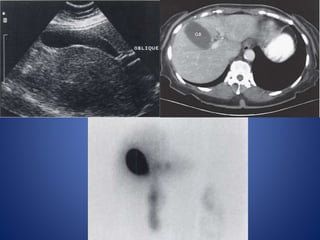

Ultrasound

Echogenic triangular cord sign

Tubular echogenic cord of fibrous tissue seen in the porta hepatis at

ultrasonography and is relatively specific in diagnosis of biliary atresia.

It is defined as more than 4 mm thickness of echogenic anterior wall of

right portal vein (EARPV) measured on a longitudinal ultrasound scan.

Gallbladder ghost triad

Atretic gallbladder, length less than 19 mm

Irregular or lobular contour

Lack of smooth/complete echogenic mucosal lining with indistinct wall

Larger hepatic arterial calibre

Positive of triangular cord sign = thickness of EARPV > 4 mm on a

longitudinal scan

5.1mm 5.4mm

Length= 1.6mm

Irregular or lobular contour

Lack of smooth/complete echogenic mucosal lining with indistinct wall

Gall bladder ghost triad

Nuclear medicine (hepatobiliary (HIDA) scan)

Cases of biliary atresia typically demonstrate relatively good hepatic

uptake with no evidence of excretion into the bowel at 24 hours.

Pretreatment with phenobarbital (5 mg/kg/day for 5 days) to increase

biliary secretion by stimulating hepatic enzymes is frequently helpful to

minimize the possibility of a false-positive study in a patient with a

patent biliary system but poor excretion.

Good hepatic uptake, but no excretion into bowel even after 24hrs.